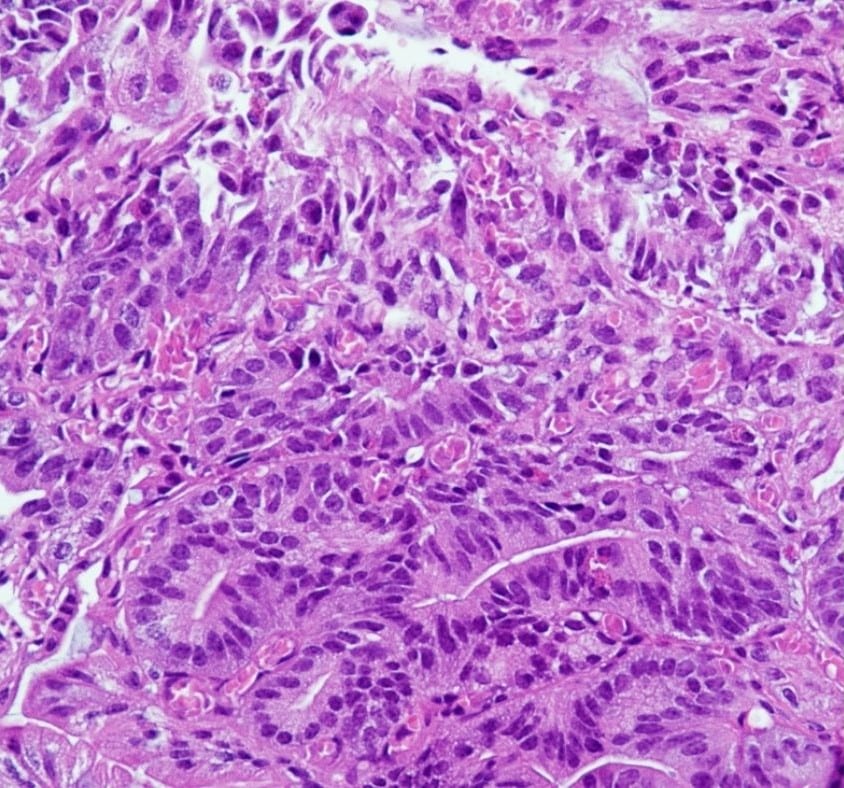

KI-Modelle, die Bilddaten verarbeiten können, sind in der Lage, auch komplexe medizinische Bilder zu analysieren. Daher bietet KI auch für die Medizin grosse Chancen. Beispielsweise könnte sie bei mikroskopischen Gewebeschnitten erkennen, um welches Organ es sich handelt oder ob ein Tumor vorliegt und welche genetischen Mutationen wahrscheinlich sind. Um beispielsweise die Ausbreitung von Krebszellen anhand klinischer Routinedaten besser zu verstehen, erforscht das Institut für Pathologie der Universitätsmedizin Mainz daher KI-Verfahren zur automatisierten Analyse von Gewebeschnitten.

Diese Erkenntnis ist insbesondere für die pathologische Routinediagnostik relevant, weil sich manchmal, beispielsweise zu Lehr- oder Dokumentationszwecken, direkt auf den histopathologischen Schnittpräparaten handschriftliche Vermerke oder Markierungen finden. Darüber hinaus wird bei bösartigen Tumoren oftmals das Krebsgewebe für anschliessende molekularpathologische Analysen händisch markiert. Die Forschenden untersuchten daher, ob auch diese Markierungen die KI-Modelle verwirren könnten.